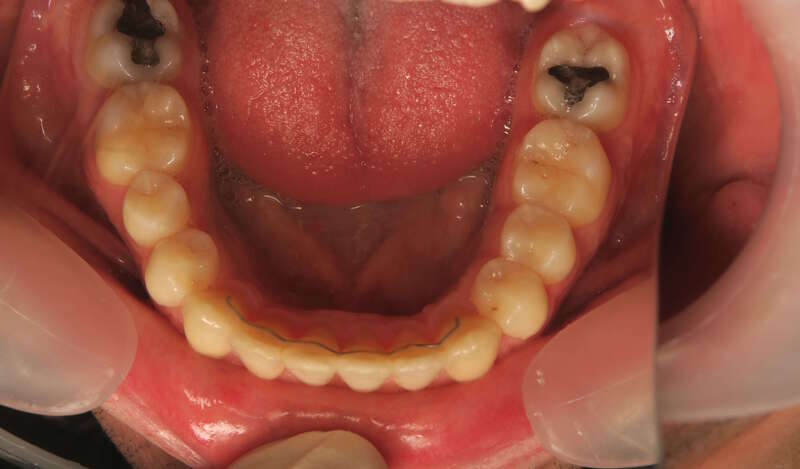

Ce cas d’interception chez un enfant de 8 ans démontre l'efficacité des aligneurs pour corriger des troubles fonctionnels précoces. Le diagnostic présentait des inversions d'articulé provoquant une déviation de la mandibule vers la gauche et un décalage des milieux.

Grâce à une coopération exemplaire et un traitement totalement indolore, l'expansion de l'arcade a permis de recentrer la mâchoire. Cette intervention a littéralement remis la croissance sur les rails, neutralisant le risque d'asymétrie faciale squelettique.

• Correction fonctionnelle : Recentrage immédiat de la mandibule et des milieux inter-incisifs.

• Prévention : Création d'un environnement favorable pour les dents définitives à venir.